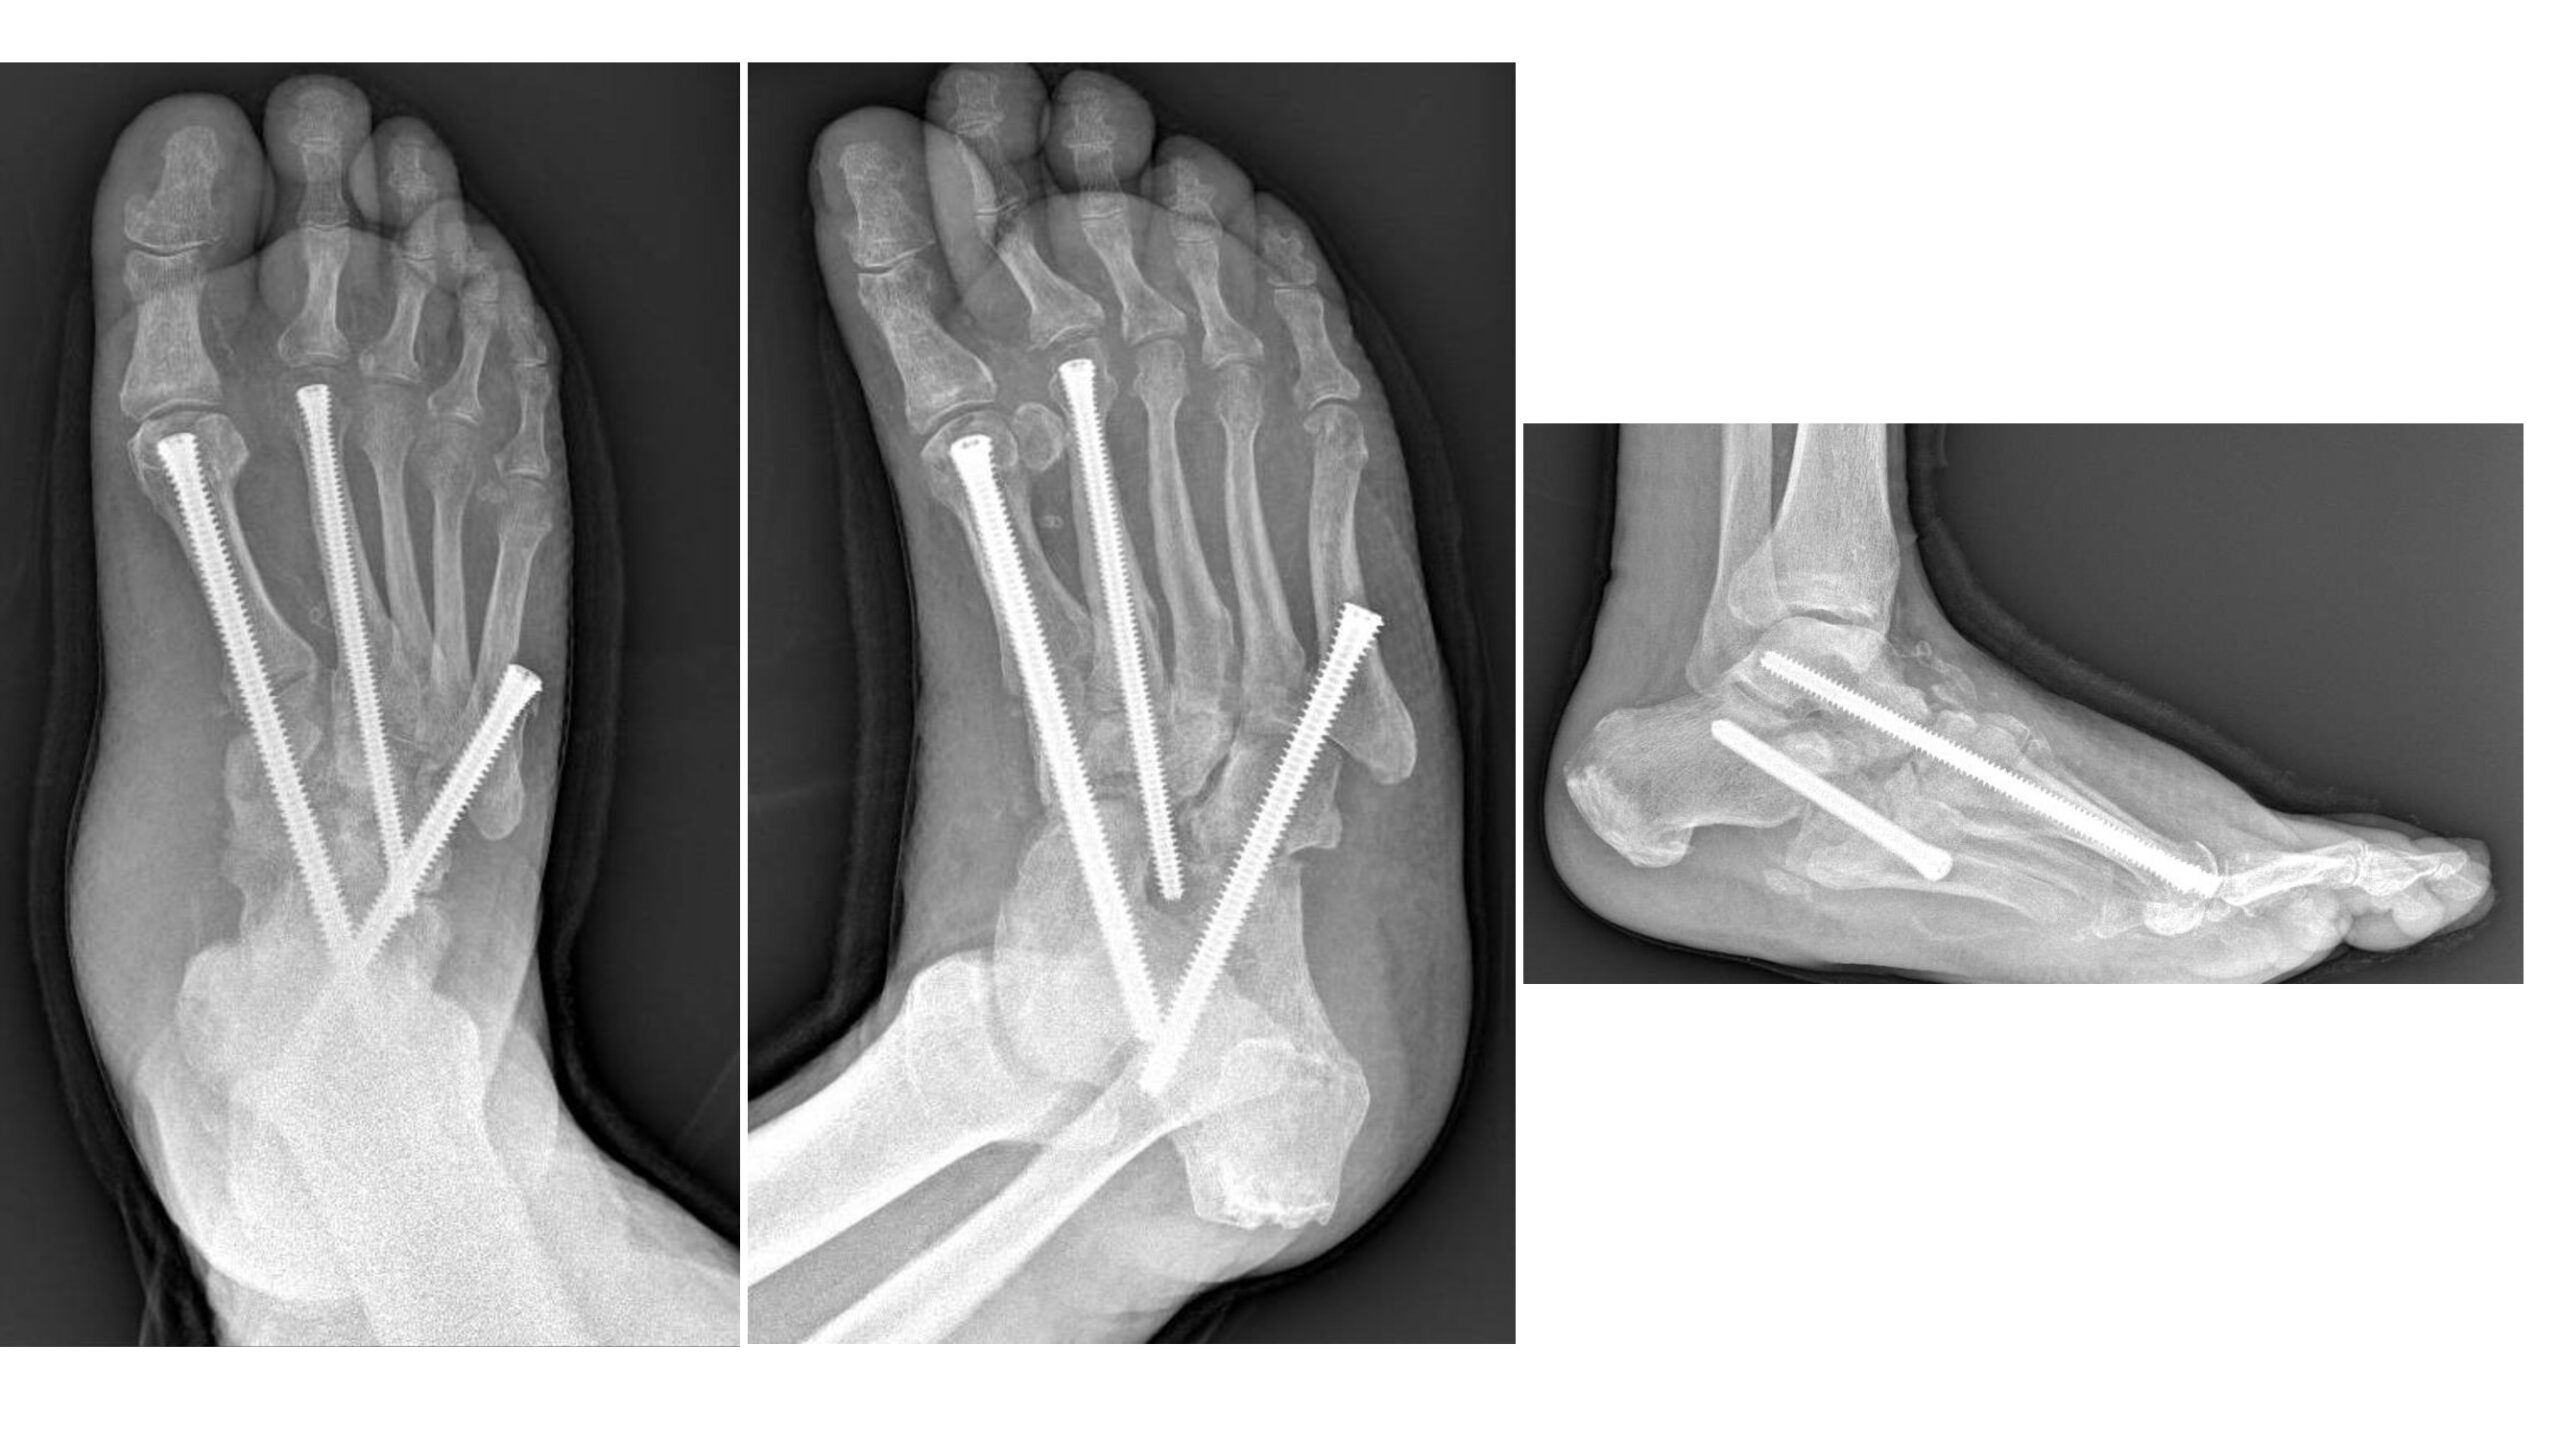

“Sono interventi che mirano a correggere deformità estremamente complesse del piede e della caviglia – prosegue il Dottor Perisano– e che prevedono una serie di procedure chirurgiche (nell’ambito dello stesso intervento), quali osteotomie correttive e successive osteosintesi. Questo consente la ricostruzione di un asse del piede e della caviglia, per permettere al paziente di tornare a camminare (in genere entro un paio di mesi dall’intervento). I pazienti affetti da questa condizione infatti non riescono più a deambulare perché queste deformità comportano alterazioni dell’appoggio, che sottopongono alcune zone del piede, normalmente non deputate a sostenere il carico, ad una pressione eccessiva che a sua volta può portare ad ulcerazioni; queste, nei pazienti diabetici (che spesso sono anche vasculopatici), possono causare infezioni gravi e profonde, che a loro volta comportano un elevato rischio di amputazione”.